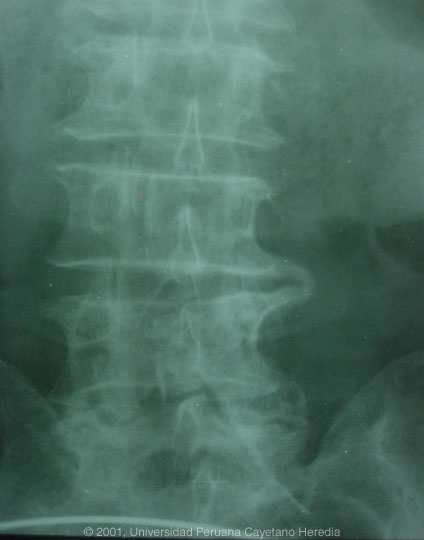

Labs/X-ray: Hct 32, WBC 8,000 with normal differential. Sedimentation rate 62. Normal alkaline phosphatase, bilirubin, and transaminases. Urine normal with normal renal function. Chest x-ray normal. Lumbar spine films shown in photograph. Blood cultures negative.

| Discussion: The major differential given the fever, night sweats, and these abnormal spine films includes Brucella, TB, and malignancy. Several features of the spine films make the lesions seen diagnostic of brucellar disease: 1) lumbar location; 2) pathognomonic bridging osteophytes between adjacent vertebrae (seen here at 2 levels) simultaneous with the presence of both osteoblastic lesions and loss of bony mass in the same vertebrae; 3) loss of disk space; 4) loss of definition of bone at top of the affected vertebrae.